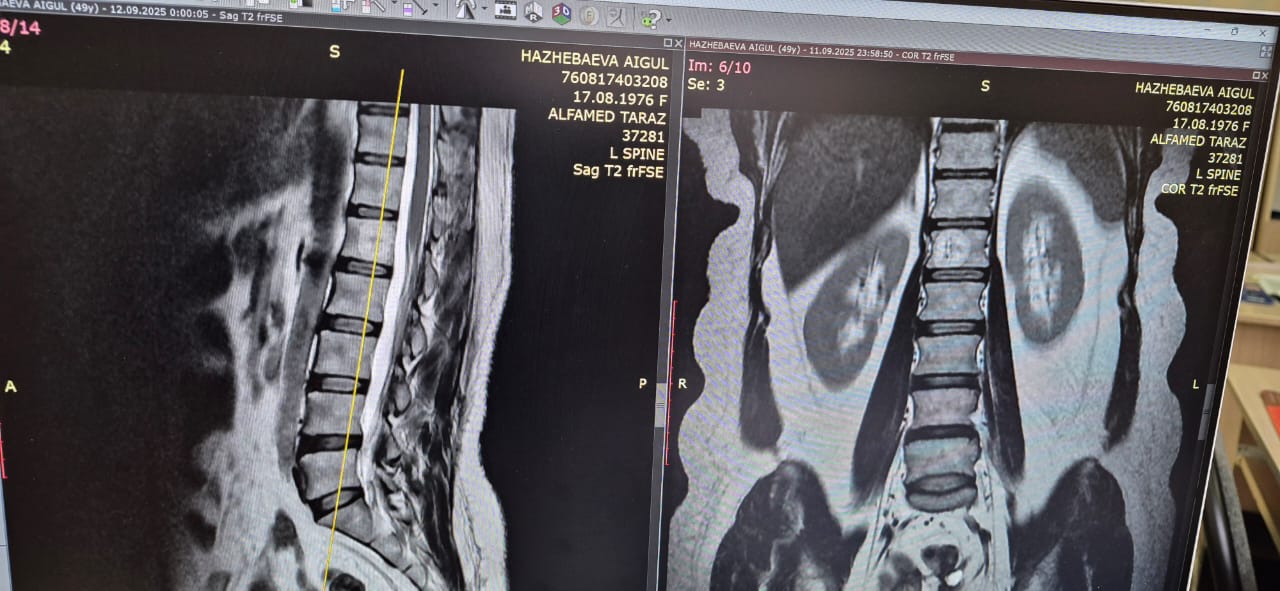

Омыртқа гемангиомасы

Омыртқа гемангиомасы — бұл омыртқа денесінің ішінде пайда болатын қан тамырлы «түзіліс». Көп жағдайда ол…